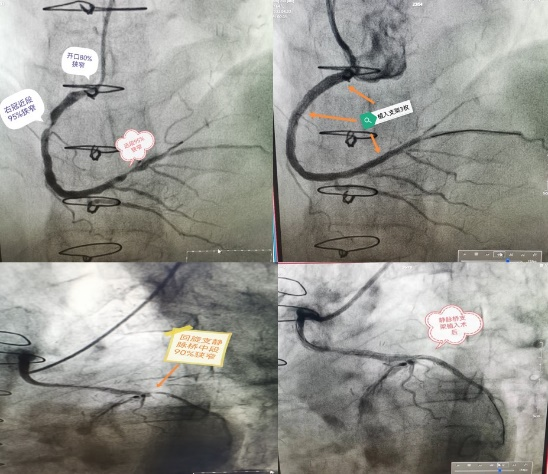

我院心内科根据造影结果进行全面分析,反复斟酌介入治疗策略,最终决定对原冠脉血管及桥血管同期进行介入治疗。在介入团队的默契配合下,心内科团队凭借娴熟的操作技术,分别开通原右冠状动脉,植入支架三枚;同时对重度狭窄的静脉桥行支架植入术。手术顺利完成,患者心肌供血得到改善。术后胸痛消失,状态良好,现已好转出院。